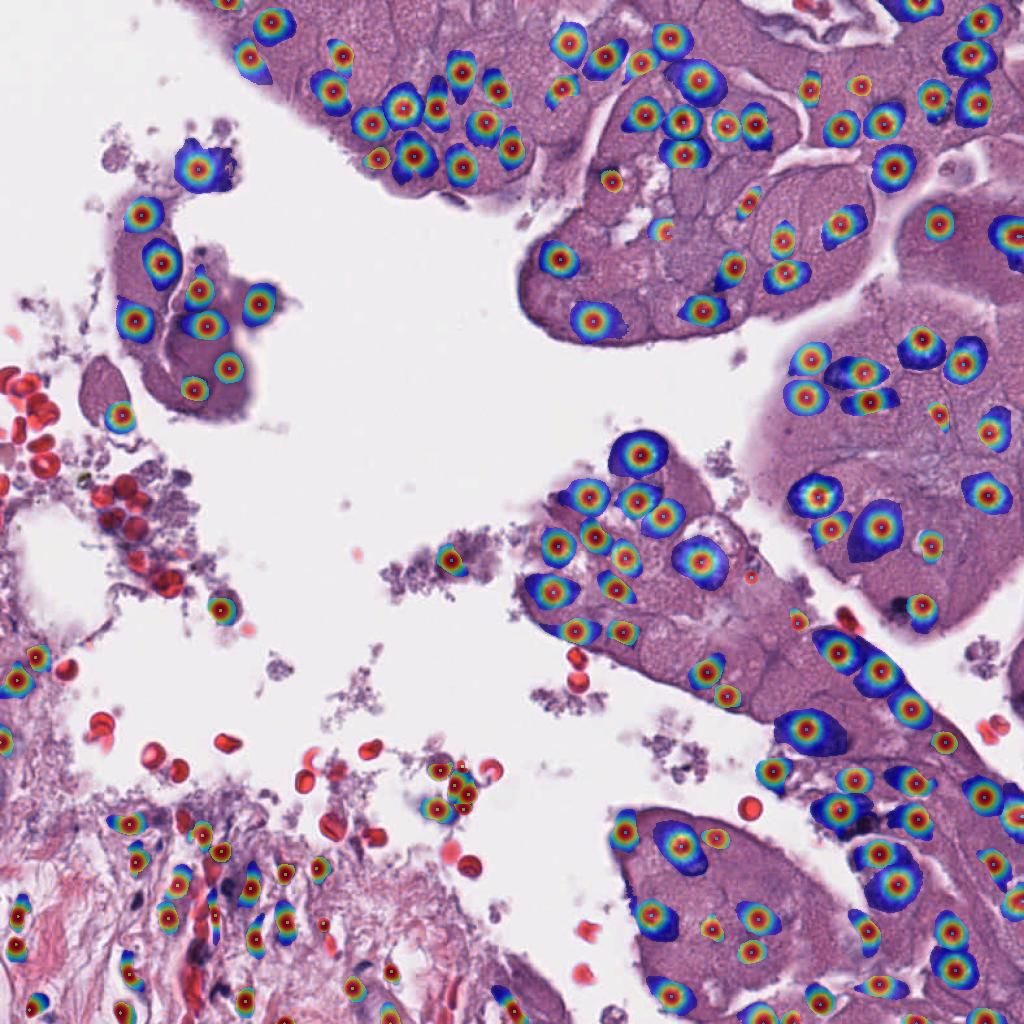

3.7 Combined Cell-Tissue Model

We combine the cell detection and tissue segmentation models, by providing and re-training the cell detection model with both the cell patch and the cropped and upsampled tissue segmentation prediction as input (Figure 4). The cell detection model ground truth configuration is chosen based on the best performance on the OCELOT validation set. Additionally, we evaluated the effect of geometrical TTA for more robust predictions, consisting of all 8 possible rotation and flip combinations. TTA was applied for both models.